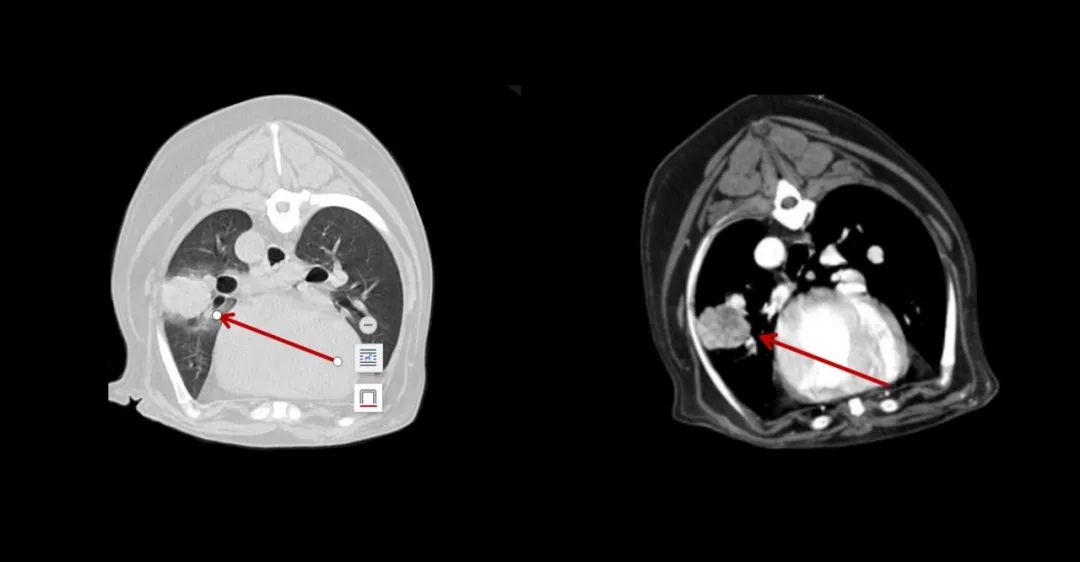

▲7歲,38kg的金毛狗近期總是嘔吐,CT全身平掃+增強(qiáng),發(fā)現(xiàn)肝和胃占位性病變。

▲7歲成年犬,乳腺癌術(shù)后1年,發(fā)現(xiàn)肺部轉(zhuǎn)移。